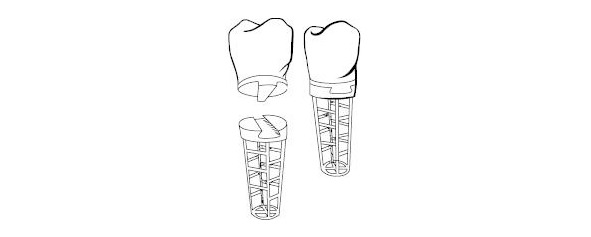

1906 год др. Эдвард Гринфелд (Greenfield) разработал цилиндрический полый проволочный имплантат из сплава иридий-платины-золота. О результатах работы было доложено в 1913 году на собрании академии стоматологии Филадельфии (США)

1937 году др. Мюллер (Muller) предложил субпериостальный имплантат из иридий-платина-золотого сплава.

1939 год др. А. Эдвард Строк (Strock) использовал винтовой имплантат из виталиума (кобальт-хром-молибденовый сплав). Имплантат был помещен в лунку сразу после удаления зуба. Через год было отмечено наличие интеграции с костной тканью.

1950—1960 годы становятся популярны субпериостальные имплантаты. Основной областью применения таких имплантатов стали челюсть с полной адентией и высокой степенью атрофии костной ткани.

Одним из направлений эволюционного развития формы имплантата можно считать игольчатый имплантат.

Игольчатый имплантат предложили Д-р Шершеве (Chercheve) и д-р Скайлом (Scialom) 1940—1980 гг

Конечно при разработки данного вида опоры не было соблюдения понятий биофизики и биомеханики поведения имплантата в костной ткани. Да и сама биомеханика, как наука только закладывалась.

Игольчатый имплантат смог обеспечить неподвижную опору в полости рта. И как этап эволюции его заслуга не подлежит сомнению.

Такие опоры не долговечны, но достаточно легко заменимы. Надежность ортопедической конструкции обеспечивается значительным количеством опор.

Следующим шагом в эволюции можно считать спиралевидные имплантаты. Грубо говоря игольчатому имплантату придали форму спирали для увеличения площади соприкосновения с костной тканью. Такое увеличение площади привело к большей стабильности имплантатов в костной ткани.

Д-р Шершеве (Chercheve) и д-р Скайлом (Scialom) 1940—1980 гг, а так же д-р Формиджини (Formiggini) начали применять спиральные имплантаты

Спиралевидный имплантат – начало эры современной дентальной имплантации.

Следующим этапом эволюции можно считать появление эндооссальных имплантатов.